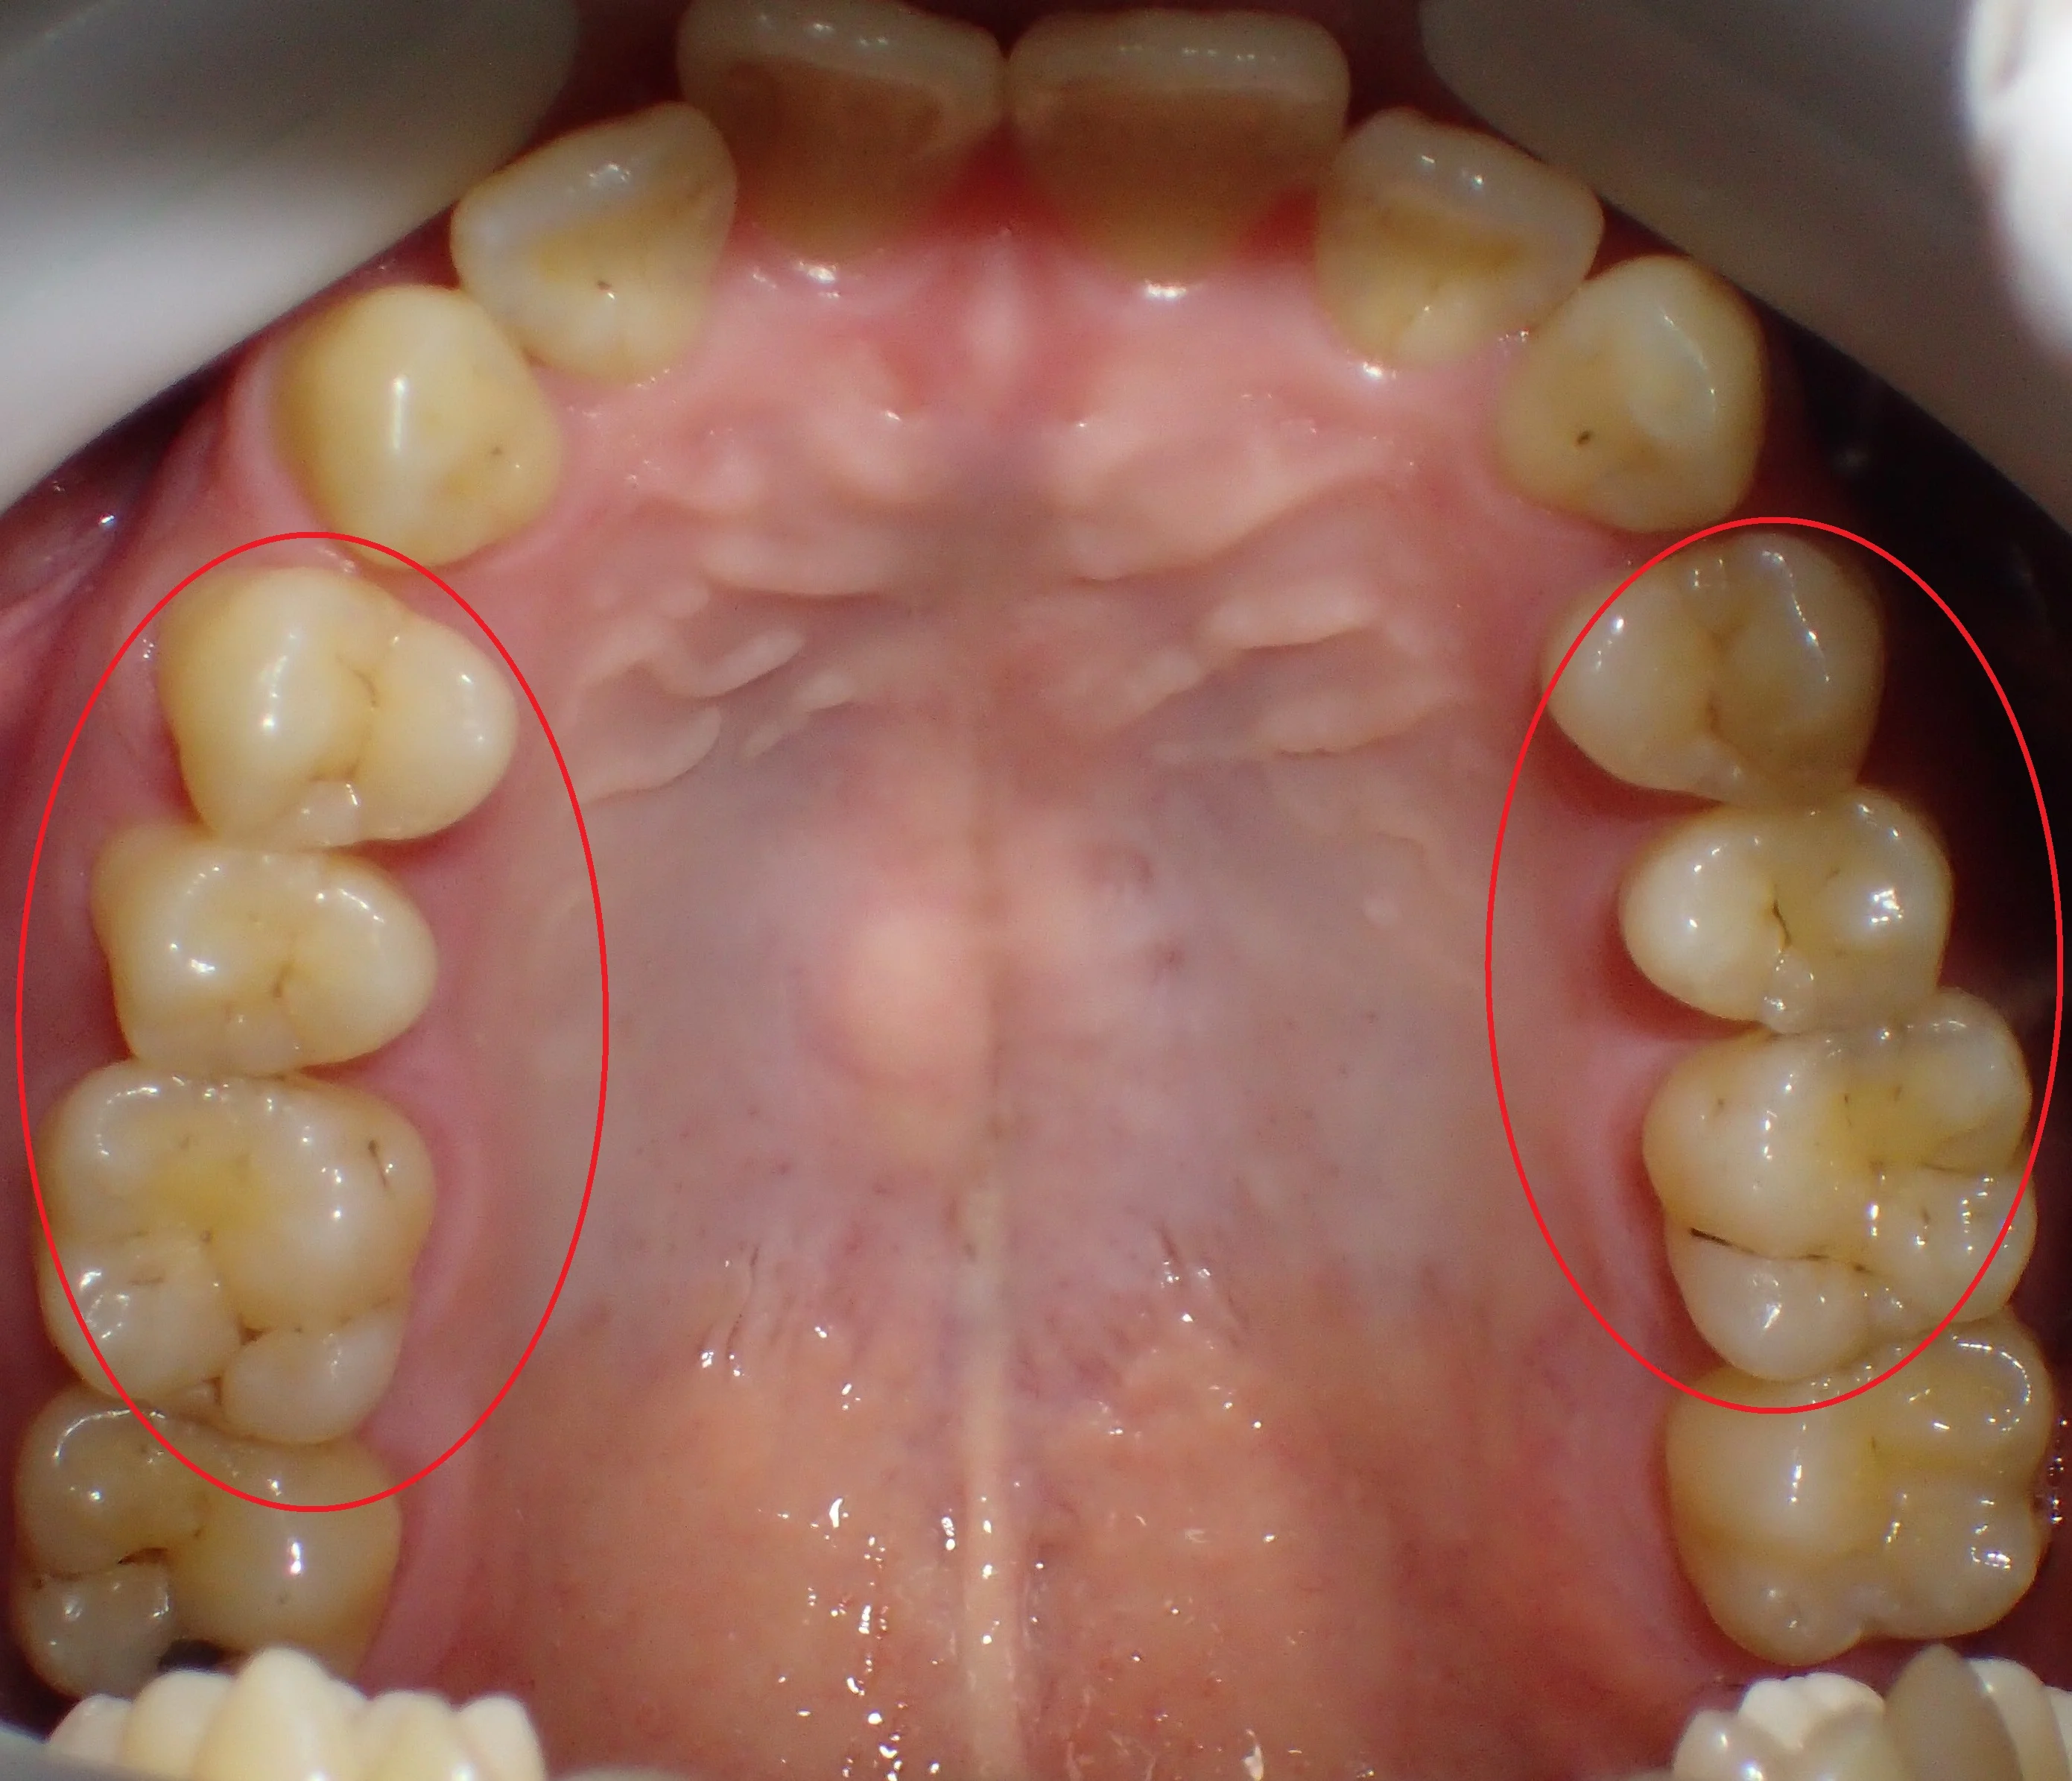

治療した箇所は、

・右上4,5,6

・左上4,5,6

治療した部位は全て元々詰めていたメタルインレーが再び虫歯になってしまった状態でした。

幸いあまり大きくは削られてはいなかったので、全てをダイレクトボンディングで治療することが出来ました。

ステイニングを行って、歯の溝の部分に色を付けると歯に立体感が出るので、急激に天然の歯っぽくなりますよね!

もう少しステイニングを弱めにしてほしいとの要望があり、他の箇所は控えめなステイニングにしました。